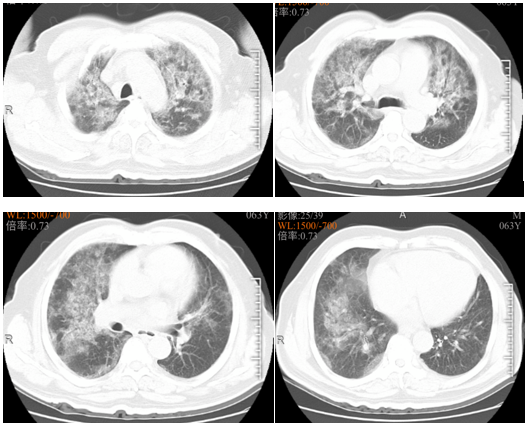

该患者本质上是由感染导致的血管炎,除了多脏器受损外,肺内应该还有出血。该患者的胸部CT比较有特点,呈向心性分布,这种情况除了考虑肺水肿、PCP、PAP外,也要考虑ANCA相关性血管炎和药物性肺损伤。该患者合并严重休克,所以还应考虑感染性疾病。二代测序结果结合临床还是有意义的,偶发分枝杆菌可以忽略,主要考虑钩端螺旋体病引起的感染。

患者于2020年7月28日开始出现胸闷、气促,考虑因腰椎病绑腹带所致,故未予以重视。于8月1日再次出现胸闷、气促加重,并伴咳嗽、痰中带血,无发热;晨起自行骑车于当地医院门诊就诊。胸部CT示:两肺炎症?肺水肿?心影增大(图1)。查血:WBC 9×109/L,N% 90.5%,PLT 47×109/L,Hb 121 g/L,CRP 268 mg/L;心功能标志物:BNP 835 pg/ml;尿常规:尿蛋白(++),尿隐血(+++),白细胞(++),胆红素(++)。

图1 患者门诊胸部CT